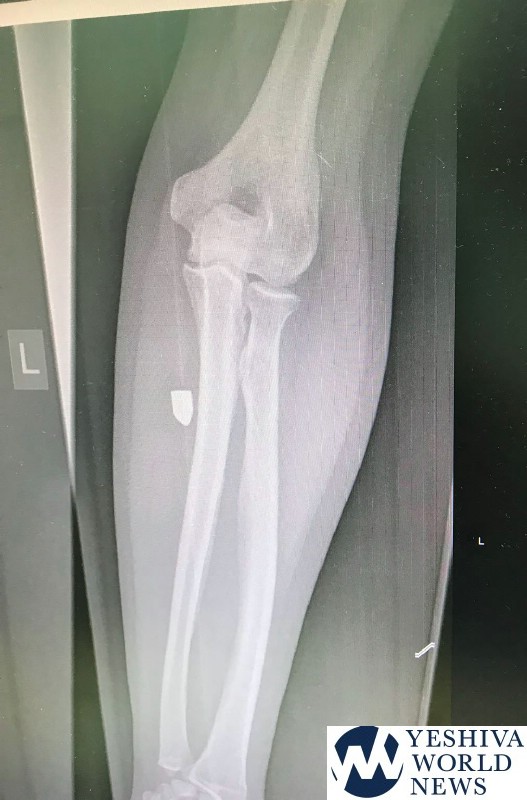

Bullet Found In Jerusalem Resident’s Arm

A resident of the Baka neighborhood of Jerusalem last week, 55, arrived at a Terem emergency clinic explaining he was seated on his balcony and suddenly, he felt a sharp pain in his left arm. He was a spot of blood on his sweater.

The x-ray revealed he had been shot with a 9mm pistol. Police were notified.